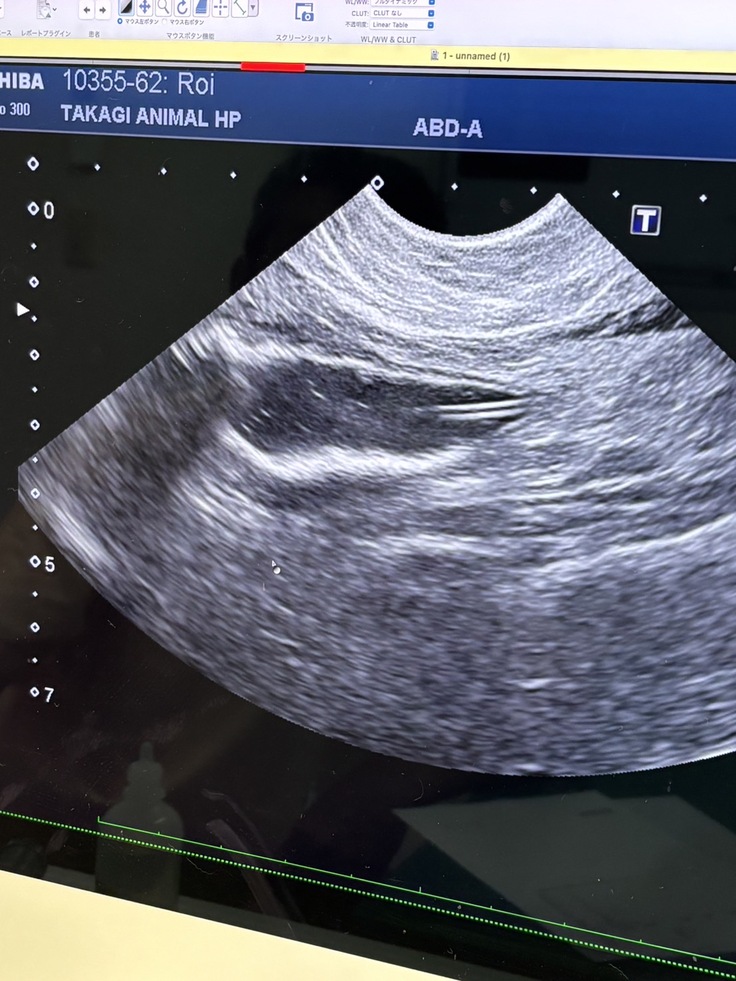

膀胱の中は砂だらけの様な尿石

そこで判明したのは尿道閉塞からの尿毒症でした。

膀胱の中は、見たこともないほど細かい砂のような結石でいっぱい。

カテーテルで尿閉を解除しなければ、生きられない状態でした。

添付した写真は、今回の猫のエコー画像と、治療の様子です。